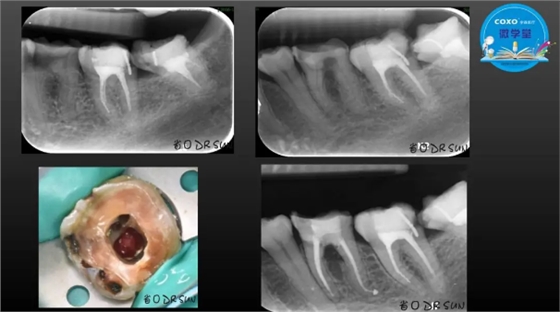

主任医师,牙体牙髓副主任, 广东省口腔医院牙体牙髓科 主任医师。2003年硕士研究生毕业,研究方向为牙体牙髓病学,擅长于牙体牙髓病的诊断、龋齿、牙髓炎、根尖周病的治疗以及前牙美容修复。